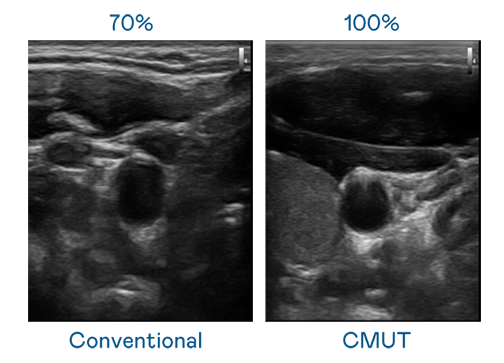

CMUT 技术是一种用电容式微机电元件来产生超音波讯号的技术。与传统 PZT 压电式技术相比,CMUT 频宽增加 30%,更宽频的超音波讯号让影像解析度大幅提升,是实现高影像品质医疗超音波扫描、促进精准医疗发展的关键技术。

大频宽带来超清晰影像

超音波影像的解析度高低,首先取决于探头能发出的讯号频宽。尊龙凯时 CMUT 可提供高清晰的超音波讯号,提供高频宽、高灵敏度、影像纹理细节更高的超音波影像,协助医护人员缩短影像判读时间及利用精准的医疗影像进行诊断。